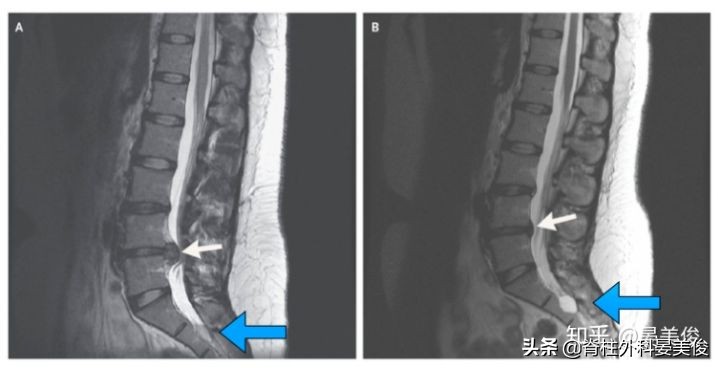

但是,就这么简单的两张图片其实很难让人信服,虽然是顶级的医疗期刊,但仍要抱着求真的心态。为什么很难信服,注意看下面的骶管囊肿,明显不一样大小,出现这样的原因就是因为两次检查的截面不一样。一个球体,当中切是最大的截面,往边上切那截面自然就小了。同理,该病例的突出也是类球体的,往突出的边缘切,那这个截面自然看着就小了,很容易造成一个突出被吸收的假象。根据骶管囊肿的不一样,以及后面的棘突位置,可以推论两次不是严格意义的同一截面。所以,需要抱着怀疑的态度来看这个病例。